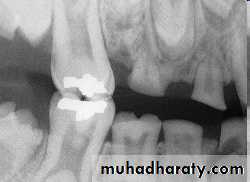

Impaction:

most often affects the mandibular 3rd molars &maxillary canines.

less commonly:

premolars

mandibular canines

second molars

CAUSES: due to obstruction from crowding.

occasionally, may be due to an abnormal eruption

path, presumably because of unusual orientation of

tooth germ.